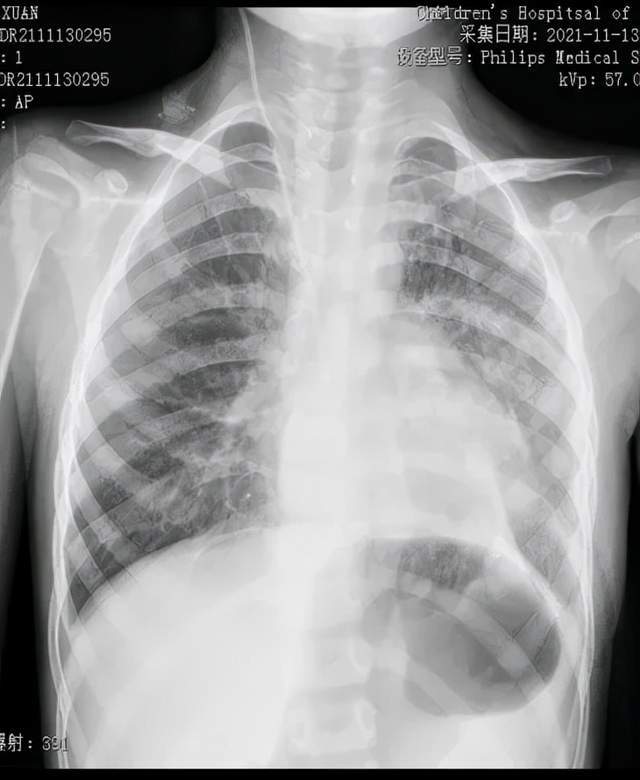

在河南省儿童医院胸心外科,程文哲医师诊断楠楠为先天性膈疝。影像资料显示,楠楠的左肺严重受压,如果继续压迫,左肺将失去功能甚至危及生命。

术前

术后在胸腔镜视野下,可看到楠楠的左侧胸腔内充满了胃和肠子,而左肺则受压变小,医生们帮助腹腔各脏器回到它们原本的位置,紧接着修补了缺损的膈肌,最后让受压的左肺重新膨开了。